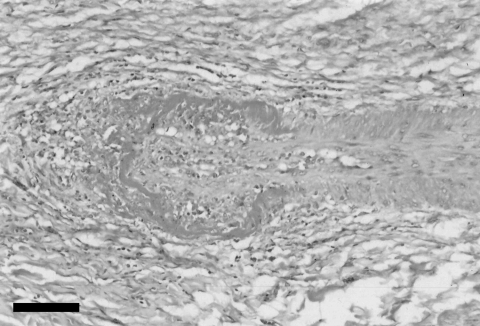

Ovine Herpesvirus 2 Infection in Foal, Brazil